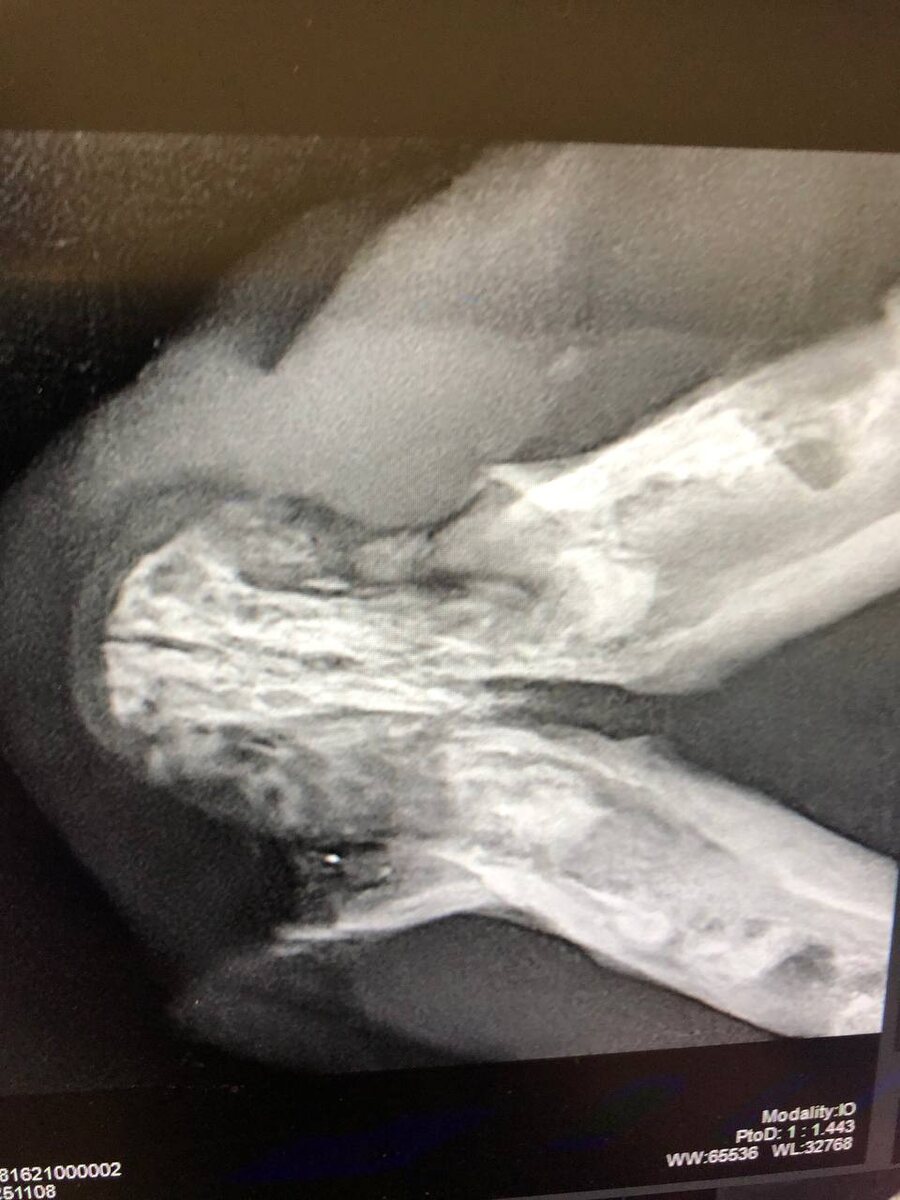

У Аси резорбция скорее все таки по II типу. Это когда как бы зубов то уже нет, но они все таки есть. Точнее их корни.

Без дентального рентгена это не увидеть.

Еще у нее уже начал устойчиво формироваться свищ на нижней челюсти, кости челюсти рыхлые, так как зубов не осталось, то и серкляж не поставить. Одна надежда, что само выправится сейчас.